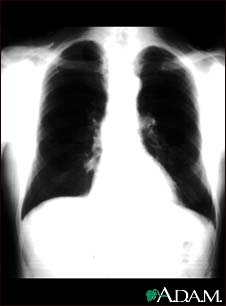

Lung nodule - front view chest X-ray

This is a chest x-ray showing a mass in the right lower lung near heart (seen on the left side of the picture).